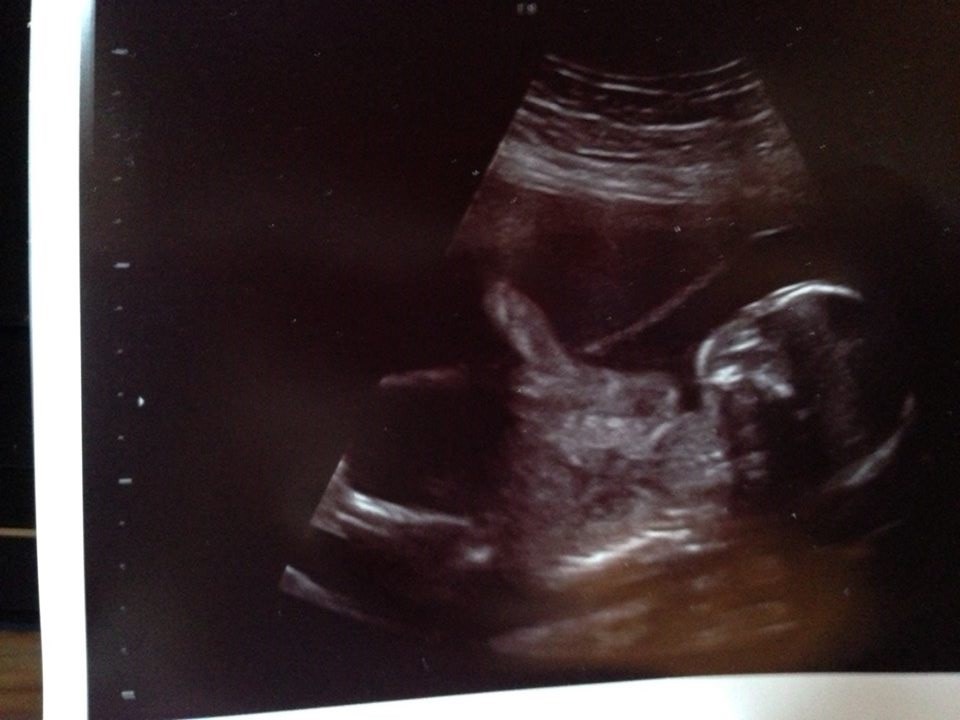

vi fik bekræftet det var en prins og en prinsesse, som begge 2 var sunde og raske.

selvom det var lidt svært at få ordentlige billeder, da de begge 2 var ekstremt livlige. og prinsen lagde og gemte sig bag ved sin søster....

Det første billede er af prinsessen, og de 2 sidste er af prinsen